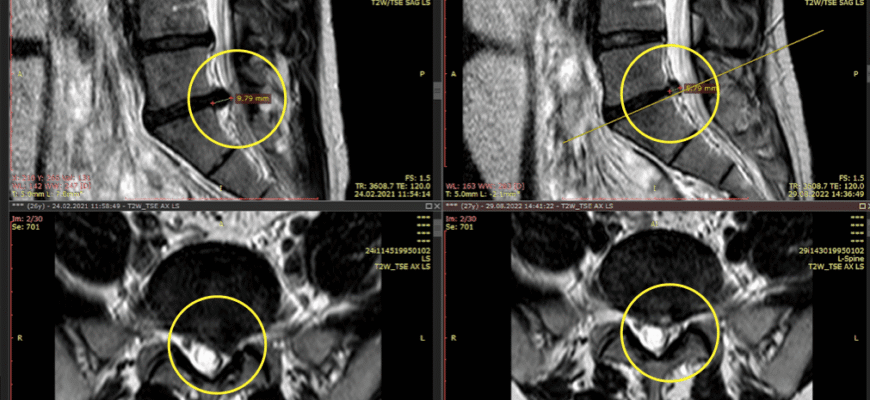

Ти приходиш до лікаря, а він такий: «Давай подивимось, що буде, якщо я натисну тут». І натискає. І одразу розумієш, що жартів не буде. Однак є ще й МРТ або рентген — на випадок, якщо раптом ти ще не переконався, що твої враження не вигадка.